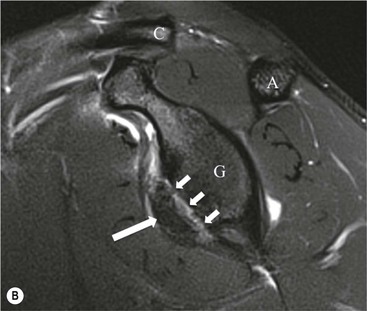

Anterior GHJ dislocation causes tearing and detachment of the anteroinferior glenoid labrum, known as a Bankart lesion. The location of the labral tear is described according to clockface terminology: 12 o'clock represents the biceps anchor, and 3 o'clock is anterior at the equator of the glenoid. Fluid signal intensity or contrast medium extending between the glenoid and labrum is the primary sign of a labral tear (Fig. 46-9). The labrum may become displaced, and it is important to assess the position of the labrum with respect to the face of the glenoid.

More severe injury may be associated with a bony injury of the glenoid rim, usually called a bony Bankart lesion (Fig. 46-10). Non-enhanced CT may occasionally be preferred to assess the size of the bony defect of the glenoid. There is usually associated impaction injury on the posterosuperior aspect of the humeral head called a Hill–Sachs defect (Figs. 46-11 and 46-12).